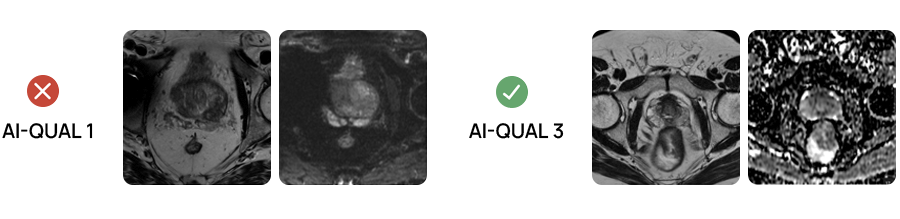

AI-QUAL™: Automated Prostate Image Quality Assessment

Quibim’s AI-QUAL™ automates the assessment of prostate MRI image quality based on the PI-QUALv2 guidelines. This tool streamlines workflows and supports diagnostic confidence.

Key benefits of AI-QUAL include:

- Automated Quality Scoring: Eliminates manual checks, saving time and reducing subjectivity.

- Standardized Reporting: Delivers consistent quality score based on PI-QUAL v2 guidelines.

- Artifact Detection: Identifies key image-degrading factors such as rectal gas distortion and metal artifacts.

- Diagnostic Confidence: Ensures radiologists work with the highest quality images.

- Seamless Integration: Designed to fit effortlessly into existing radiology workflows.